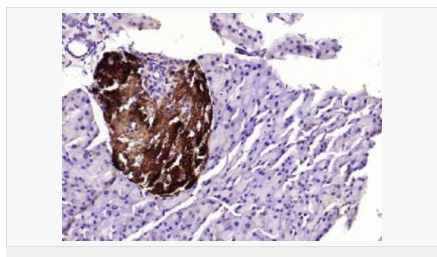

| 產(chǎn)品應(yīng)用 | WB=1:500-2000 ELISA=1:5000-10000 IHC-P=1:100-500 IHC-F=1:100-500 ICC=1:100-500 IF=1:100-500 (石蠟切片需做抗原修復(fù)) not yet tested in other applications. optimal dilutions/concentrations should be determined by the end user. |

| 細胞定位 | 細胞漿 |